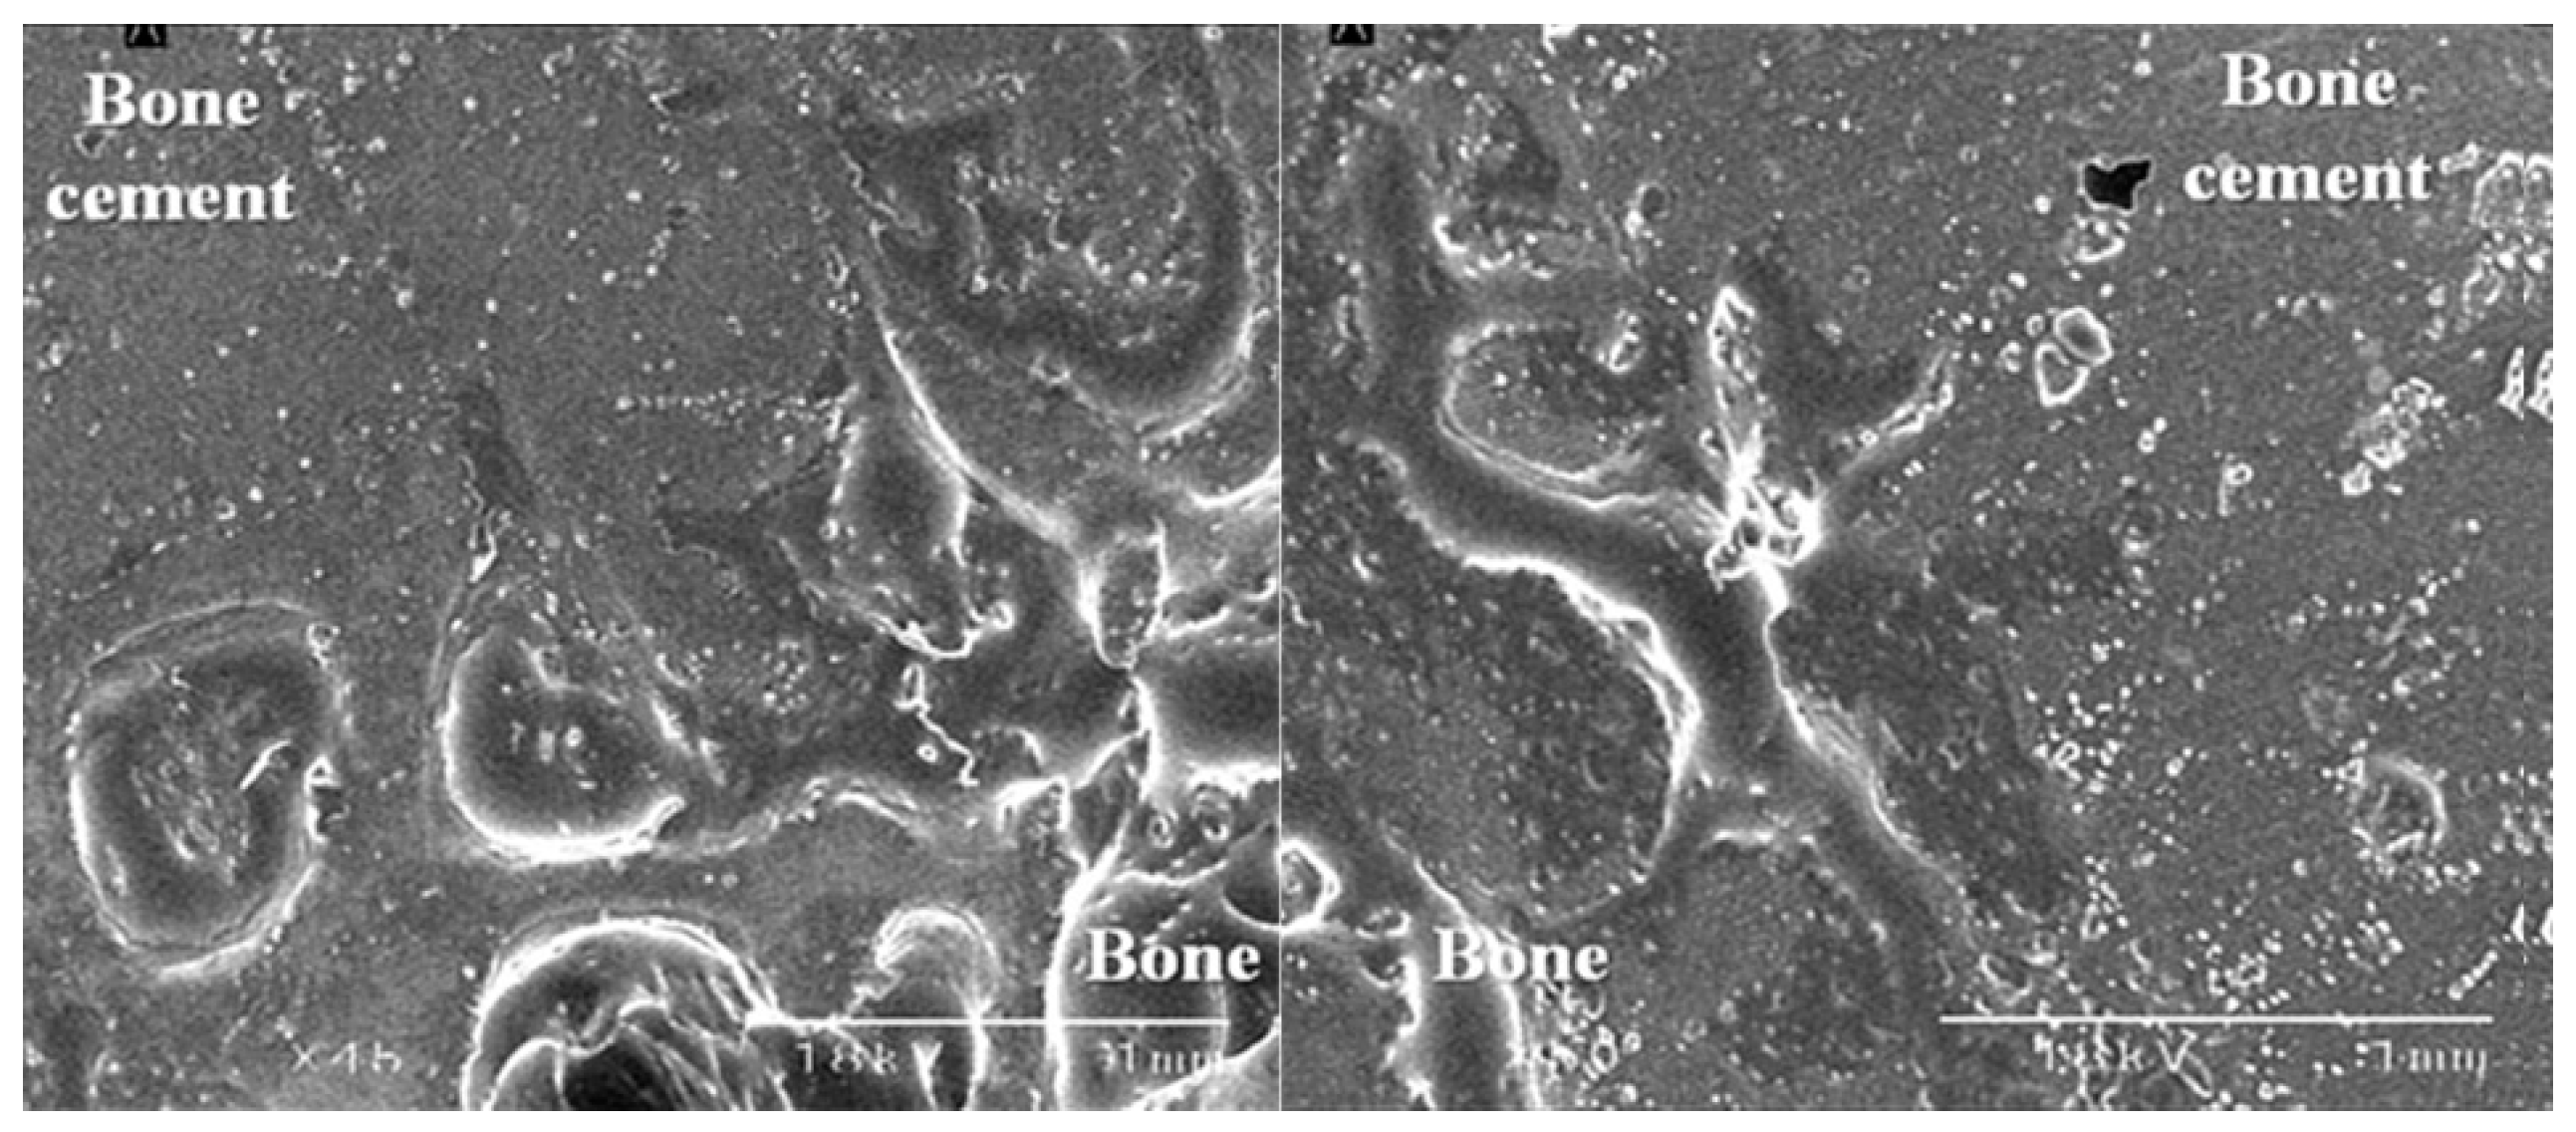

3.3. The Bond Strength at the Bone–Cement Interface

4. Discussion